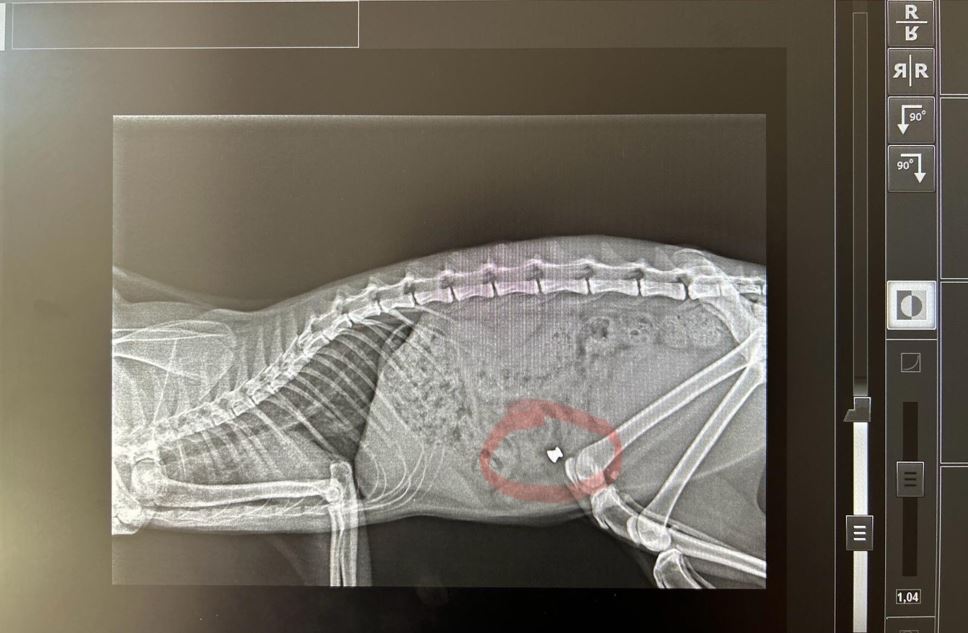

La situazione è estremamente preoccupante, con alcuni gatti che sono stati uccisi e solo due sono riusciti a salvarsi grazie all’intervento tempestivo di un veterinario. Una foto della lastra mostra chiaramente il proiettile nel gatto prima che venisse operato e salvato dal medico veterinario Prof. Gianni Marinacci di Rende. Europa Verde ha deciso di offrire una ricompensa a coloro che forniranno filmati o fotografie che possano identificare gli autori di questi vili gesti. Inoltre, il partito presenterà denuncia alle autorità competenti e, nel caso venga identificato l’autore di questi delitti, chiederà un imponente risarcimento da destinare a gattili o associazioni di volontari che si occupano di piccoli felini.